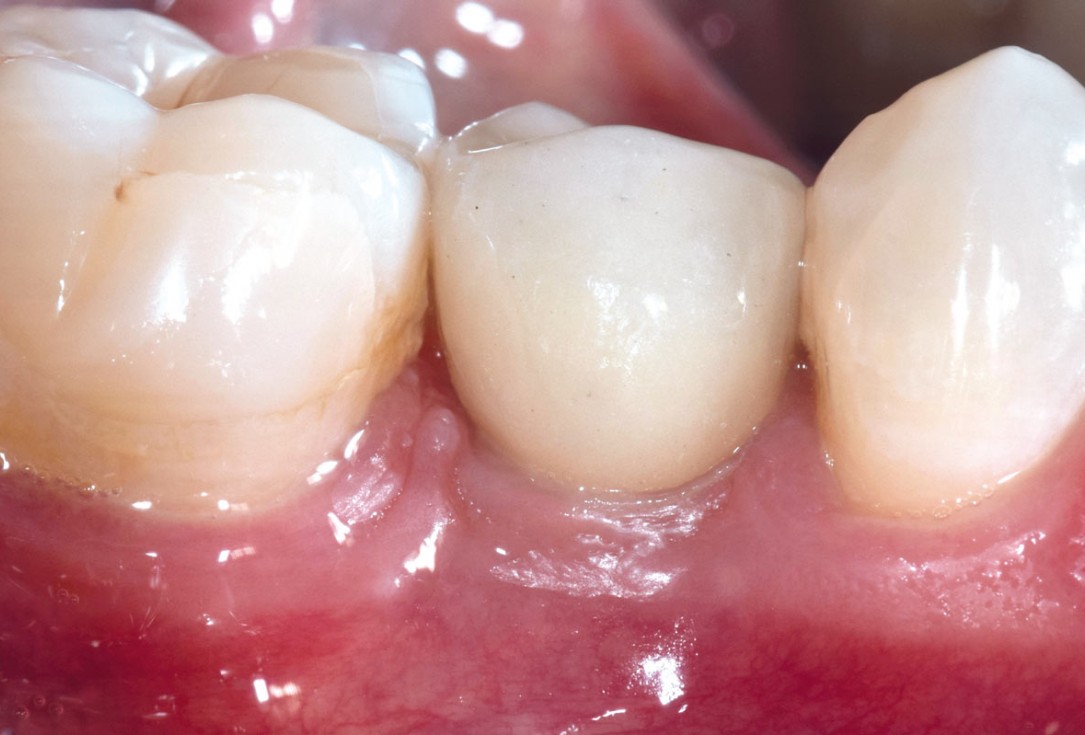

16/17 - Follow up at 2 years presenting stable soft tissues with final restorationApplication of mucoderm® for soft tissue management around single implants at second stage surgery Dr. C. De Annuntiis

17/17 - X-ray at 2 years presenting stable hard tissuesApplication of mucoderm® for soft tissue management around single implants at second stage surgery Dr. C. De Annuntiis